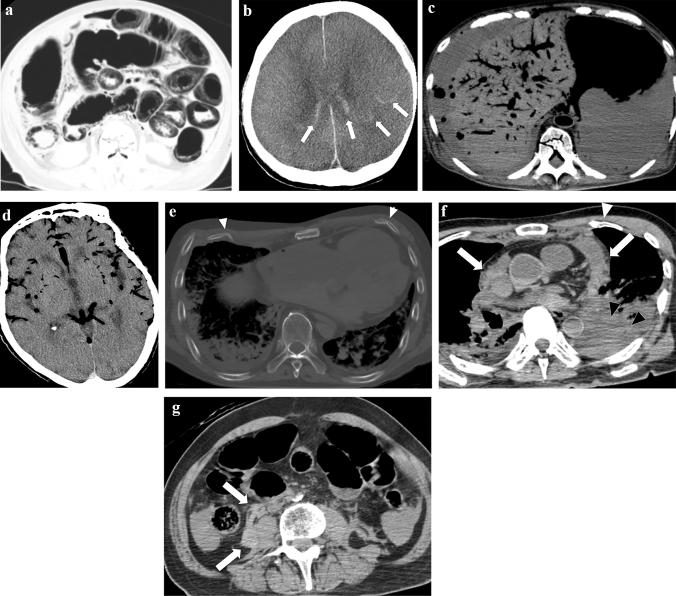

Postmortem computed tomography (CT) is an essential tool for investigating the causes of death. Postmortem CT has characteristic imaging findings and should not be interpreted in the same manner as clinical antemortem images. In analyzing the cause of death in in-hospital death cases using postmortem images, it is crucial to understand early postmortem and post-resuscitation changes. In addition, it is essential to understand the limitations of diagnosing the cause of death or significant pathology relating to death on non-contrast-enhanced postmortem CT. In Japan, there has also been social demand to establish a system for postmortem imaging at the time of death. To facilitate such a system, clinical radiologists should be prepared to interpret postmortem images and assess the cause of death. This review article provides comprehensive information regarding unenhanced postmortem CT for in-hospital death cases in daily clinical practice in Japan.

死后计算机断层扫描(CT)是研究死亡原因的重要工具。死后 CT 具有特征性的影像学表现,不应与临床生前图像以相同的方式进行解读。在使用死后图像分析院内死亡病例的死亡原因时,了解早期死后和复苏后变化至关重要。此外,了解在非增强死后 CT 上诊断死亡原因或与死亡相关的重要病理学的局限性也很重要。在日本,也有社会需求建立死亡时的死后影像学系统。为了促进这样的系统,临床放射科医生应该准备好解读死后图像并评估死亡原因。这篇综述文章提供了关于日本日常临床实践中院内死亡病例的非增强死后 CT 的全面信息。